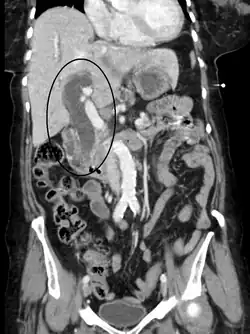

- Obstrução das vias biliares por:

- Cálculos biliares (pedra na vesícula biliar)

- Cistos

- Tumores benignos do fígado, sistema biliar ou pâncreas

- Estenose